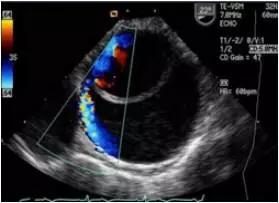

夹层病变时真腔中的血流速度快,假腔中的血流速度相对慢。有时还可显示真假腔间相交通的血流,主动脉瘤时增宽的主动脉腔内的血流速度常较慢。此外,位于主动脉根部的主动脉夹层和主动脉瘤,常可显示不同程度的主动脉瓣关闭不全。

多普勒超声不仅能检出主动脉夹层分离管壁双重回声之间的异常血流,而且对主动脉夹层的分型、破口定位及主动脉瓣返流的定量分析都具有重要的诊断价值。

应用食管超声心动图。结合实时彩色血流显像技术观察升主动脉夹层分离病变较可靠。对降主动脉夹层也有较高的特异性及敏感性。